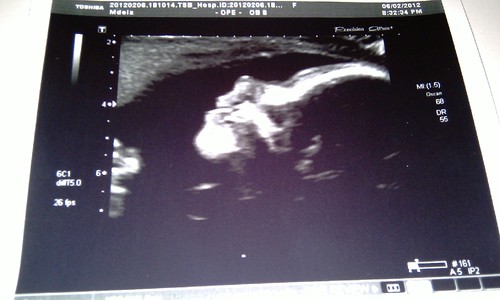

34 Semanas

Já só faltam 7 semanas para conhecer o meu Vicente!!!

Ver pela primeira vez a cara do meu filho! :)